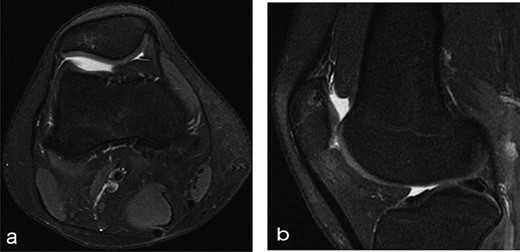

A 14-year-old female dancer presented with increasing right knee pain and functional disability without any trauma. Her pain was retropatellar pain that often radiated medially or laterally from the patella, exacerbated by climbing stairs, running and squatting. She was unable to perform any sports activities. Examination revealed peripatellar tenderness and crepitus, full range of motion and the knee was stable. Radiological examination included both MRI and computed tomography of the knee were performed at the beginning. MRI showed osteochondritis dissecans at the area at the superolateral facet of the patella in the deep subchondral area as shown in Fig. 1. This was appropriately treated conservatively with 6 months of reduced load and protected weight bearing without relief of symptoms. She quit sport activity for 2 years and then another MRI was performed Fig. 2. After 2 years we opted for adipose-derived mesenchymal stromal cells (AD-MSCs) intra-articular therapy according to the procedure described by Tremolada et al. [9]. The patient’s parents were given written information regarding the use of AD-MSCs therapy, including relative risks of this therapy and also relevant treatment alternatives that could otherwise be explored. Postoperative radiological evaluation was performed at 6 months and 12 months after AD-MSCs procedure as shown in Figs. 3 and 4. Postoperative clinical evaluation was performed using IDKC, Lysholm and Tegner scores (Table 1). After surgery, patients began a McConnell program of lateral retinacular stretching, patellar taping and vastus medialis obliquus muscle exercises. The patient was encouraged to swim and cycle to reduce impact loading. Using AD-MSC, she reported a complete relief of pain after 1 year from the procedure. Routine MRI follow-up 2 years later showed evidence of appreciable improvement in cartilage volume and osteochondral architecture at the site of injury. Early MRI T2 mapping at 6 months indicated that the area of cartilage regeneration exhibited high water content suggestive of immature cartilage or fibrocartilage morphology. Later T2 mapping at 18 months after the procedure, indicated progressive maturation of cartilage from deep to superficial layers with more hyaline like cartilage morphology. Limitations of the study are lack of arthroscopic intra-articular visualization and classification of the patella lesion.

Six months after MSC treatment in (a) axial and (b) sagital T2-weighted of MRI T2 sequences the OCD in patella showed that area of cartilage in regeneration and fill of high water content suggestive of immature cartilage or fibrocartilage morphology (c) same lesion in sagital T1 weighted MRI sequences.